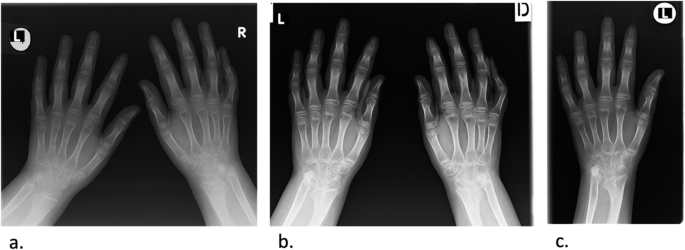

During the 2017, at the age of 13, the trial of mycophenolate mofetil (MMF) followed by the trial of cyclosporin was initiated, but the patient nevertheless remained GC dependent. Both shoulders, elbows, radiocarpal joints, metacarpophalangeal (MCP), proximal interphalangeal (PIP), distal interphalangeal (DIP) joints and both knees had restricted range of movement, and repeated IAGI were necessary to alleviate the symptoms. Finally, in 2018, the treatment with Janus kinase (JAK) inhibitor tofacitinib was initiated, which lead to gradual amelioration of musculoskeletal symptoms and improvement of inflammatory markers and overall well-being, as well as to the weaning of systemic GC. Moreover, as the swelling of the wrists subsided for the first time in many years, Madelung deformity was noticed by clinical examination. Interestingly, it was only then, in 2019, that the deformity was for the first time described on x-ray (Fig. 2), although x-ray and MRI imaging of both hands were previously performed on many occasions in order to assess the inflammation (Figs. 3 and 4). Nevertheless, subsequent analysis by experienced musculoskeletal radiologist revealed characteristic bilateral signs of Madelung deformity dating back in 2015 and 2017 (Fig. 3), with the MRI showing the Vickers and radiotriquetral ligament (Fig. 4). The finding of those two ligaments allowed the distinguishing between Madelung deformity and pseudo-Madelung deformity, which includes post-traumatic and post-infective forms, forms associated with Turner syndrome, multiple hereditary exostoses and Ollier disease [23]. Unfortunately, due to the parent’s refusal, no further radiological assessment was performed, so we have not documented the other important aspects of Madelung deformity, such as radial shortening and diaphysis bowing, nor the mesolimbic shortening of limbs characteristic for Leri Weill syndrome.

The anteroposterior radiograph of both hands at the age of 10 (a) and 13 (b), and of the left hand at the age of 14 (c). Note the bowing of the distal radius, an increased radial inclination (~ 30°) with the deformation of the carpus that acquired a triangular appearance and widening of the distal radial-ulnar joint bilaterally, which are the typical features of Madelung deformity. Dorsal subluxation of the ulnar head is not seen as lateral images of the wrist were not taken. Osteopenia of carpal bones and periarticular osteopenia of MCP, PIP and DIP joints related to JIA are present. No relevant changes are observed during the time